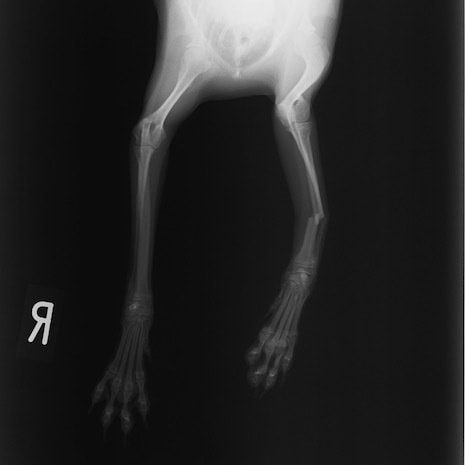

ペルシャ猫 11ヶ月齢 雄

他院にて左大腿骨遠位の成長板骨折(salter-harrisⅠ型)が認められており、治療相談を目的として来院。当院にて、キルシュナーワイヤーを用いたピンニングにより骨折部位の整復を行いました。術後の経過は良好で、現在も経過観察中です。

術前レントゲン